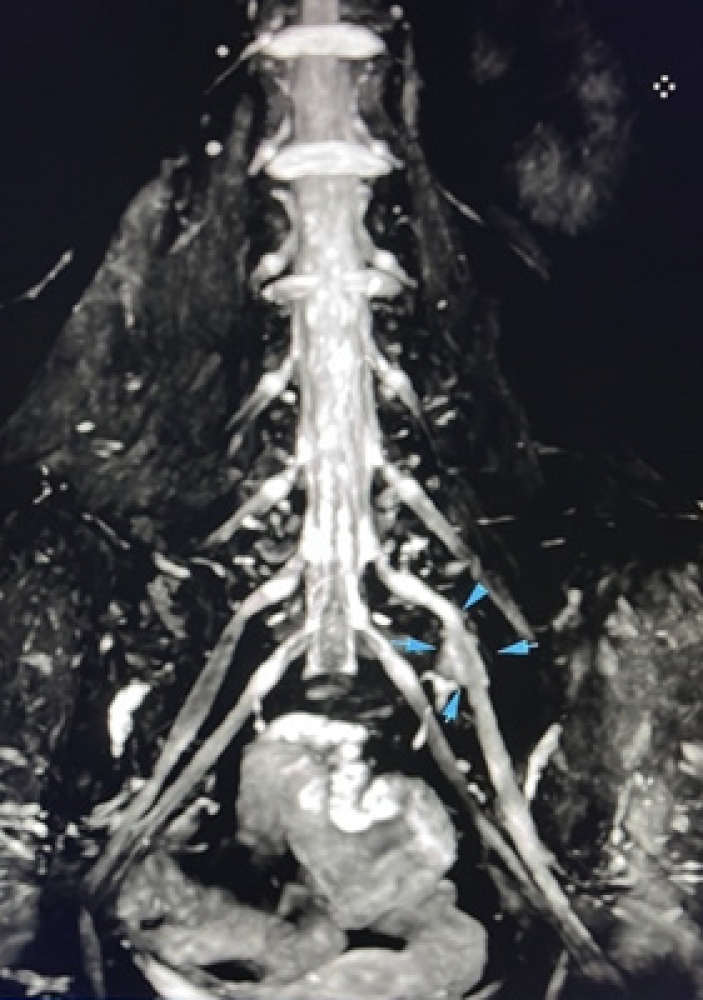

To further evaluate the suspected plexus lesion, a contrast-enhanced lumbosacral MRI (MR neurography) was obtained. On a 3D STIR (Short Tau Inversion Recovery) sequence focused on the lumbosacral plexus, there was mild fusiform thickening and contrast enhancement observed along approximately a 3 cm segment of the left L5 nerve, distal to the neural foramen (Figure 1). These MRI findings were consistent with an inflammatory plexus lesion (plexitis) affecting the lumbosacral plexus, specifically the L5 component. Post-contrast T1-weighted MRI showed enhancement of the left L5 nerve/root (Figure 2). No compressive mass or structural lesion was seen. Based on the combination of EMG and MRI findings, the patient was diagnosed with idiopathic lumbosacral radiculoplexus neuropathy coexisting with CRPS of the left lower extremity.

Figure 1. 3D MR neurography image illustrating mild thickening and enhancement of the left L5 nerve (arrow) distal to the neural foramen, consistent with an idiopathic plexitis